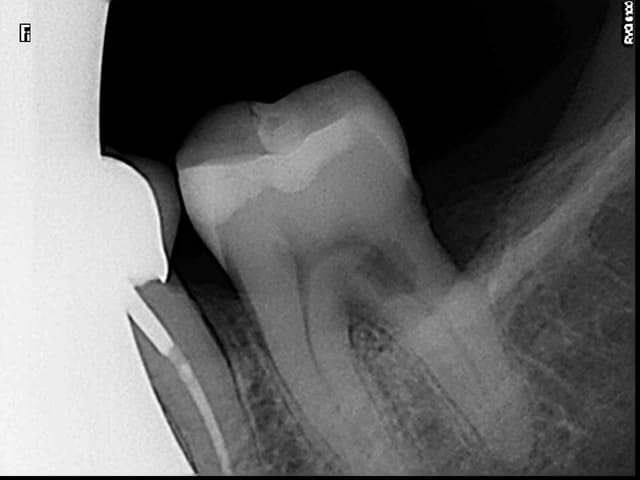

Bonjour, la patiente présente les signes d'une pulpite débutante sur 37 et à la radio j'ai trouvé çà : une lacune (érosion interne?) de forme atypique...j'ai pris plusieurs clichés avec angulations différentes.

Quelqu'un sait il ce que c'est ? Le diagnostic ? J'envisage le TC, des précautions particulières ?

Si ce n'est pas une lésion externe (noter la perte osseuse au niveau de la racine distale), ce serait plus une résorption interne qu'une érosion interne, non?

Je confirme, aucune lésion externe vestibulaire, distale ou linguale. Résorption interne ou lacune à angles nets, quelles sont les causes ? Traitement spécifique ou endo traditionnelle ? (je suis la patiente en paro depuis plusieurs années).

Entre la première et la deuxième radio, tu as clairement un décalage de la lésion.

De plus les contours du canal distal sont très nets sur toutes les radios

On devine une résorption osseuse sur cette racine distale

Donc pour moi tout indique que c'est externe

Même si je n'en suis pas certain à 100%. On voit bien le canal distal défini en effet derrière la lésion de résorption. Après je pense que les clichés sont décalés ne le sont pas assez pour se faire une meilleure idée mais il semble que la lésion soit décalée entre les clichés 1 et 2 par rapport au canal donc externe aussi.

C'est vrai que mes clichés ne sont pas assez décalés mais j'ai bien examiné la dent et la patiente à un parodontite chronique généralisée. Bref, je pense toujours à une résorption interne, verdict vendredi, à suivre...